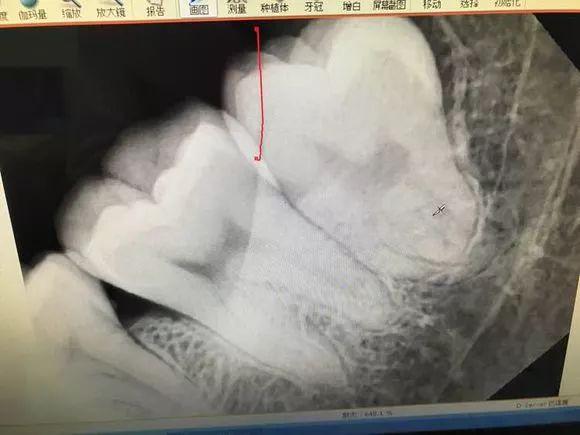

傳說(shuō)中收費(fèi)14000的牙長(zhǎng)這樣子——

難度三噩夢(mèng)模式

后介紹一下,牙根彎曲,騎在下頜管上的智齒...由于下頜管內(nèi)神經(jīng)豐富,拔除的時(shí)候需要極度小心,而且看長(zhǎng)相也知道這種模式的拔牙,難也貴!